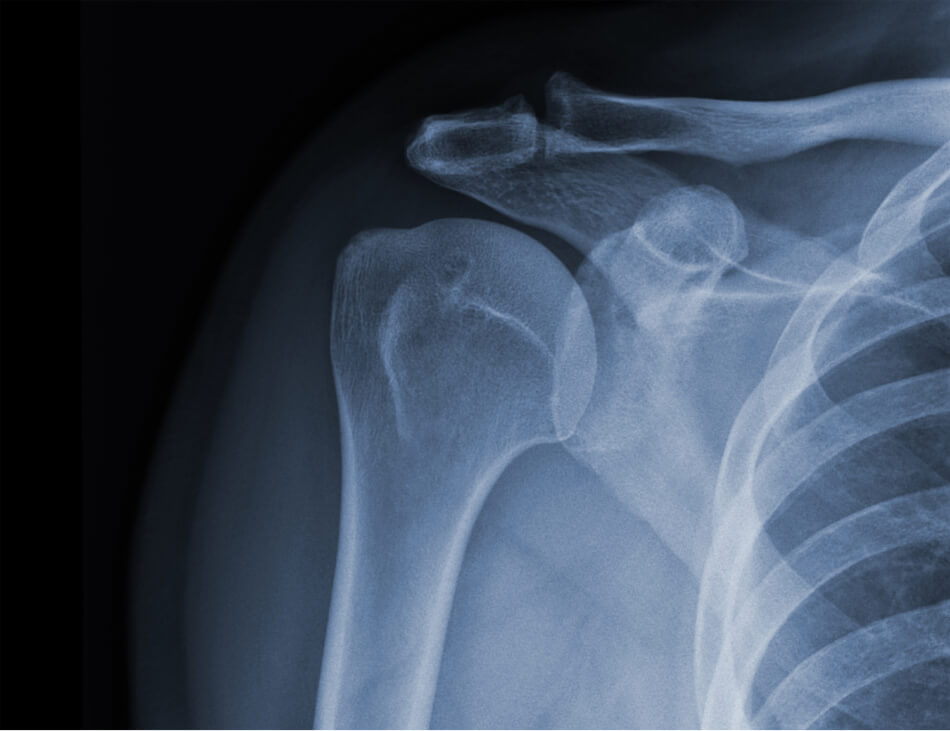

野球肩とは?

野球肩は投球障害肩とも呼ばれ、ボールを投げる動作によって肩周辺に痛みが発生するスポーツ障害のひとつです。

野球肩は肩関節周囲の筋肉や靭帯、骨、関節包が損傷することによって起こります。

損傷した部位によって肩の前方、後方、上腕(二の腕)など痛む場所が変わるのが特徴です。

インピンジメント症候群

野球肩の中で最も多いのがインピンジメント症候群です。

野球の投球動作、腕を上に振り上げる動作を繰り返すラケット競技でも発症します。

動作を行うたびに肩甲骨の突起である肩峰や肩関節の靭帯が上腕骨に衝突し、関節内に炎症や痛みが生じる野球肩のひとつです。